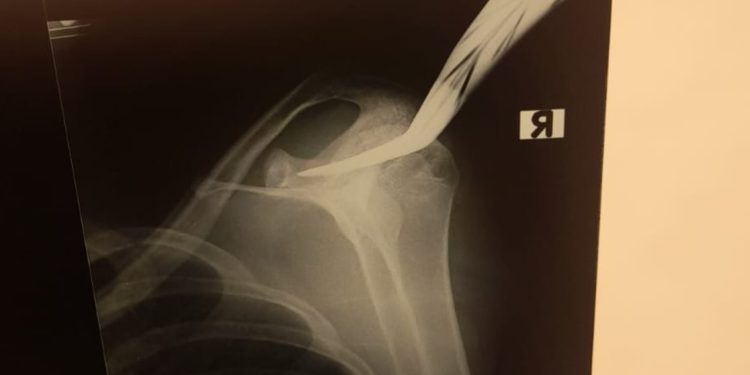

Jeffry juga menyebutkan bahwa korban kini sedang dalam penanganan medis intensif. Luka yang diderita TS akibat bacokan masuk ke tulang skapula, tepatnya di bahu sebelah kanan, dengan luka sepanjang 4 sentimeter.

“Korban dirujuk ke RS Sardjito untuk penanganan lebih lanjut,” tutup Jeffry.